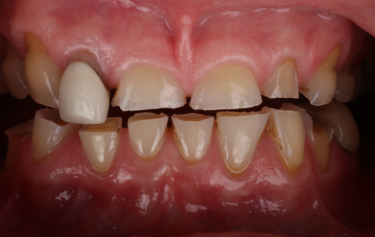

Figure 1: Full smile – before

Figure 2: Frontal retracted view – before

This 58-year old female patient presented showing advanced tooth surface loss and loss of occlusal-vertical dimension (OVD) with passive overeruption of her anterior segment. She was struggling to enjoy the foods she loved and over the last few years had recoiled herself from any form of social engagement as she found public eating very difficult. She was very embarrassed of her smile and only smiled with her mouth closed. She had been in a profession with a lot of stress and had suffered in the past with gastric reflux. She also admitted to drinking 2 cans of carbonated soft drink every day for over 30 years.

Her main concern was the size discrepancies and tooth wear that was obvious within her smile. She had a low lip line and slightly deficient buccal corridors (Fig. 1). She was posturing into a pseudo-class 3 occlusion with passive overeruption of all her teeth, more noticeable on the anterior upper and lower labial segment (Fig. 2). She had missing posterior teeth and so all her mastication was on a reduced dental arch.

Her teeth showed tooth surface loss and passive eruption of the both the upper and lower anterior segment with excessive upper gum on show during forced wide smiling. The diagnosis of severe attrition and tooth surface loss was made, as a result of previous acidic reflux, stress-related parafunction, and a highly acidic diet, which lead to the erosion and subsequent collapse of the arches and loss of occlusal-vertical dimension.